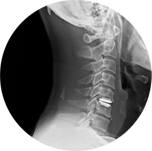

固定式的做法也稱「椎間融合術」,早期曾用自體身上取出的骨頭,但由於多了一個傷口,且取骨處疼痛目前已經幾乎沒人使用了;取而代之的是不同材質人工支架(如PEEK cage, 圖一、二)代替椎間盤,置於椎體中間。 若有頸椎脫位或穩定性不良則常需輔以鈦合金固定物(圖三、四)。 目前健保可申請的是PEEK支架,一個約三萬元左右,若申請通過時只需付十分之一的部分負擔。優點是較經濟,但缺點是須戴頸圈固定三個月,以及該節被固定融合後的頸椎間活動度會受減少。

圖一

圖二